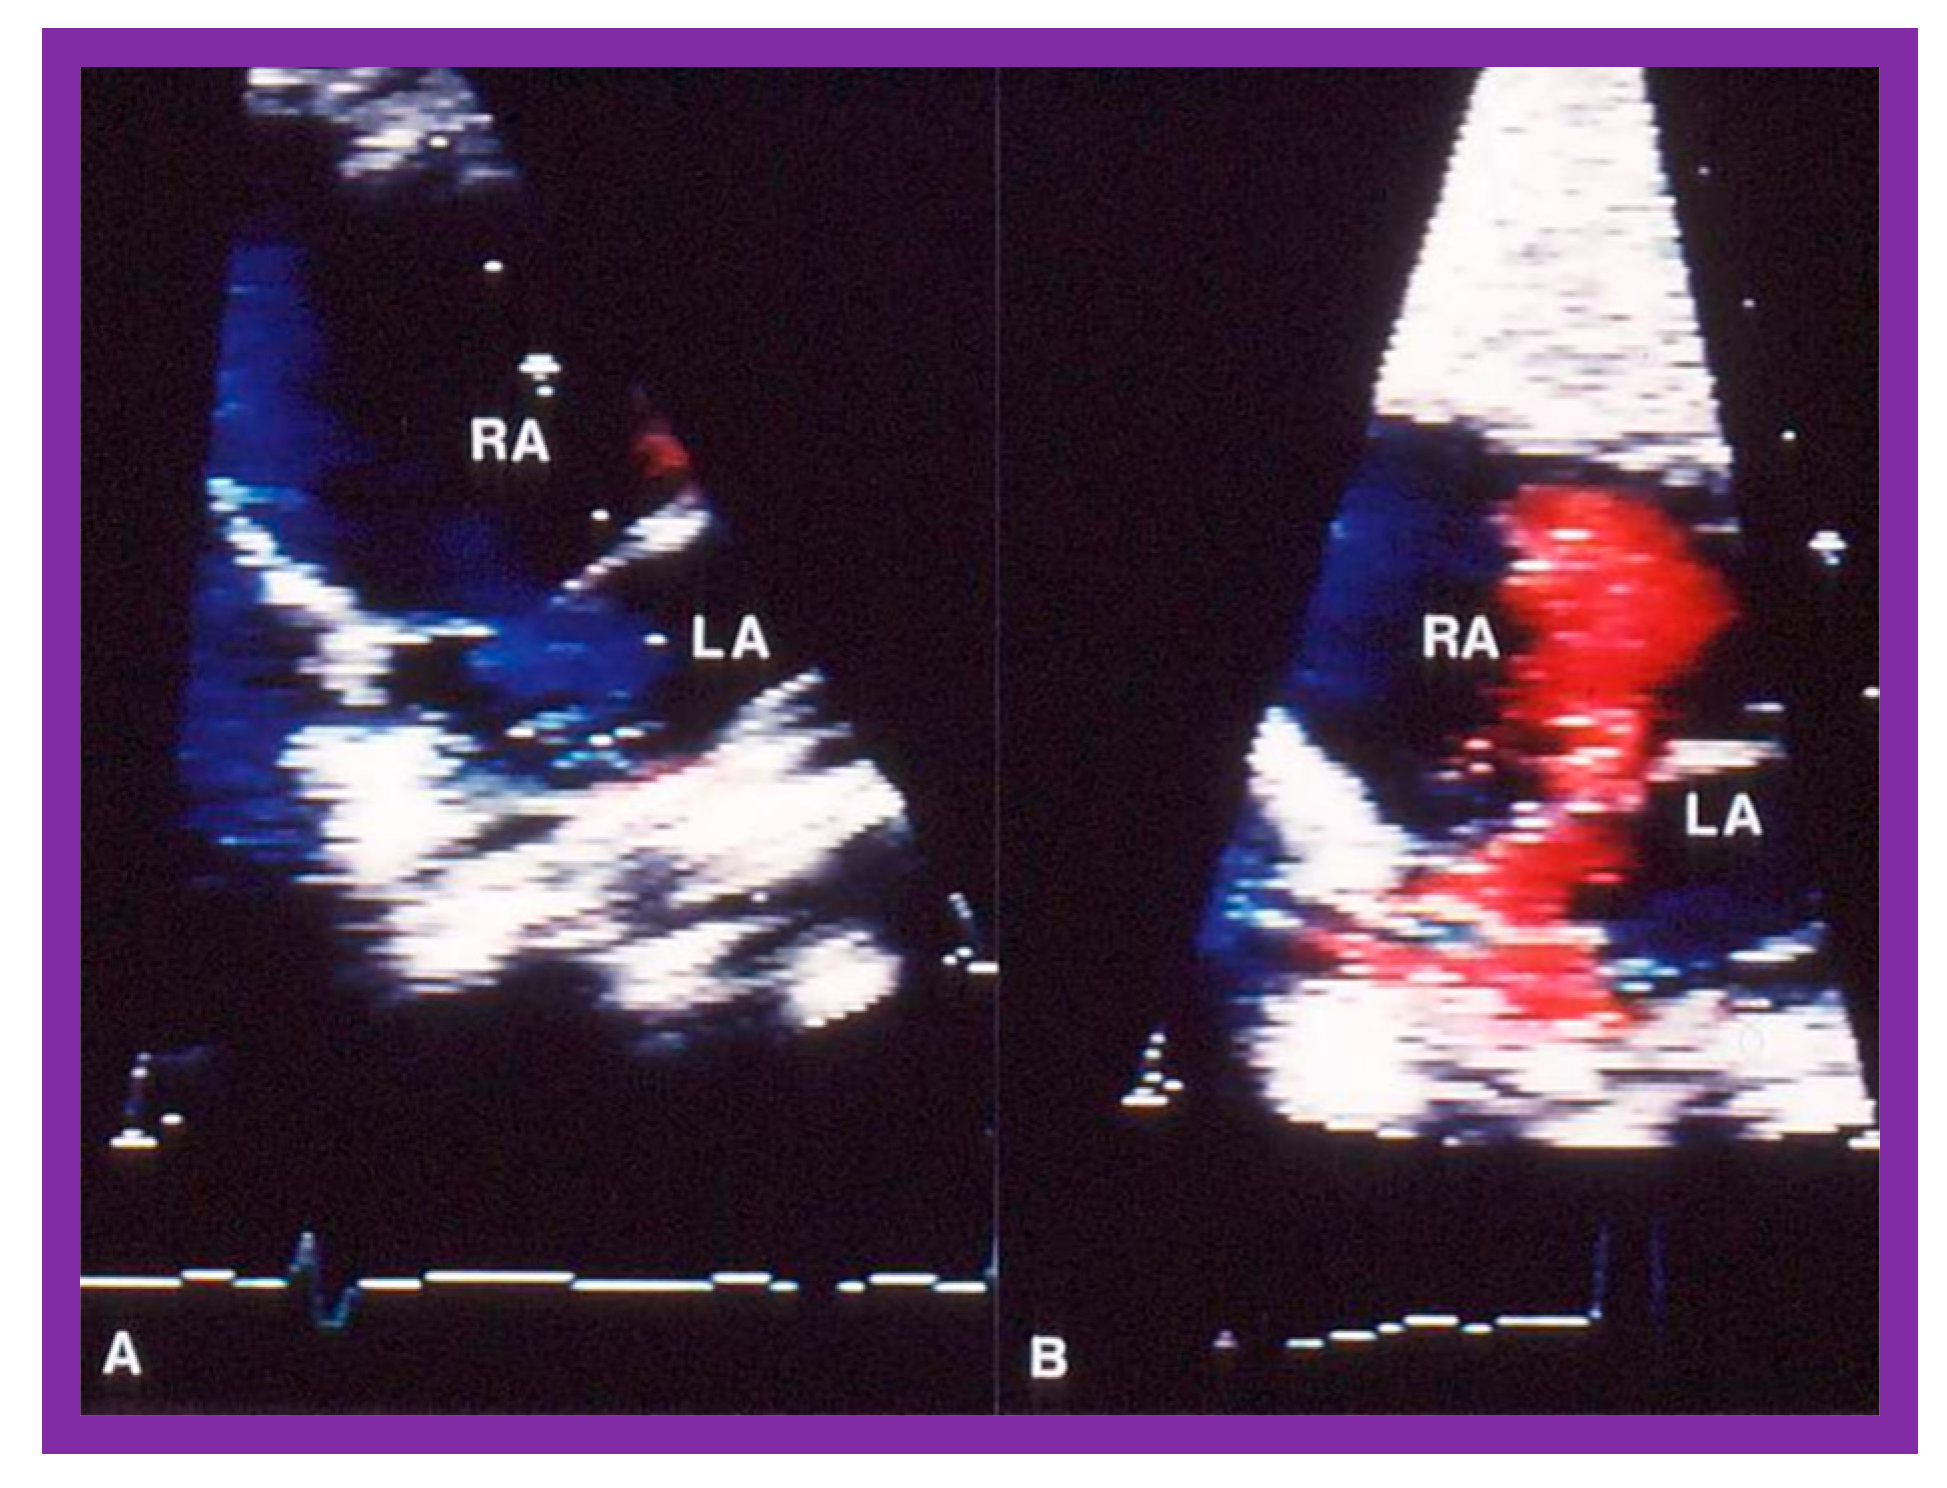

2.3. Changes in Right Ventricular Filling

Abnormalities of RV filling and reduced compliance of the RV musculature are anticipated in children with RV outflow tract obstruction in a manner like those seen in patients with left ventricular outflow obstruction [25,26]. Similar abnormalities were shown in patients with RV hypertrophy associated with PS [27]. However, Vermilion and associates [27] could not demonstrate any change in the RV filling abnormalities and compliance parameters after successful BPV [27]. Because these findings are at variance with our clinical observations, we examined this issue with the aid data from our patients [28]. Of a total of 75 patients who had BPV, 10 patients had arterial desaturation due to right to left shunt through the patent foramen ovale (PFO) (Figure 12A). In this subset of patients, the peak pulmonary valve gradients decreased (118 ± 38 mmHg vs. 28 ± 17 mmHg; p<0.001) immediately after BPV. The right to left shunt across the PFO got reversed (Figure 12B). Simultaneously, the systemic arterial O2 saturations improved from 83 ± 8% to 94 ± 5% (p<0.001), the pulmonary flow index increased from 1.9 ± 0.5 to 2.7 ± 0.6 L/min/m2 (p<0.001), and the pulmonary to systemic flow ratio got elevated from 0.7 ± 0.1 to 0.95 ± 0.1 (p<0.001). When the information on each child was examined, the arterial O2 saturation improved in every child (Figure 13) [28].

Improved O2 saturation after BPV is linked to eliminated or diminished right to left shunt across the PFO. The only change between pre- and post- BPV status is reduced gradients across the pulmonary valve with consequent reduction of RV afterload. This reduced RV afterload, we believe, has improved RV filling with resultant decrease in right to left atrial shunt [28]. Conceivably the Doppler data [27] are not sufficiently sensitive to perceive improved RV filling following BPV.

Figure 12. Selected video frames of the atrial septum, demonstrating a right-to-left shunt by color Doppler, across the patent foramen ovale prior to balloon pulmonary valvuloplasty (A) which has changed to a left-to-right shunt (B) 24 hours later. LA, left atrium; RA, right atrium. Reproduced from Reference [21].